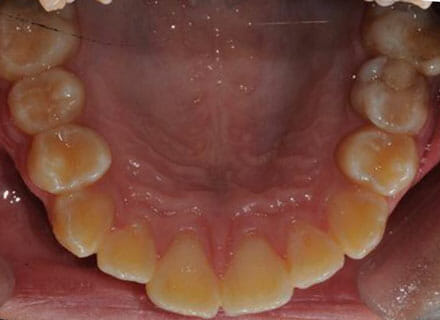

Fixing protruding teeth upper and lower and crowding – no extractions

this patient didn’t like the teeth because they pushed forwards and were sticking out and pushing out her lips. She thought that she looked like she had too many teeth and not enough space. In 12 months we pulled all the teeth back, pulled them together, and lined them all up. No teeth were extracted because we made room by expanding the jaws.